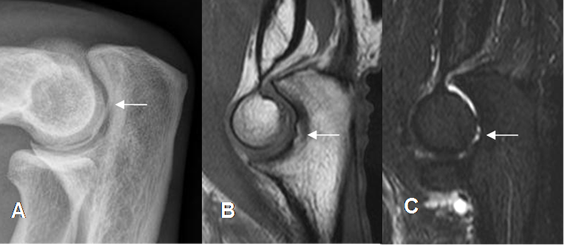

El seudodefecto del capitel se observa en la parte externa. Se valora en cortes axiales y debe tener bordes lisos, sin alteración en la señal de intensidad. Debe diferenciarse de fracturas, lesiones osteocondrales y quistes. (Fig 7 y 8).

Fig 7. Seudodefecto del Capitel.

A: Rx AP. B: RM sagital en T1 y C: RM coronal en T1.